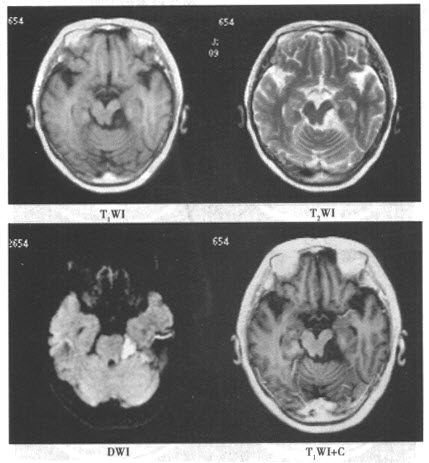

患者,女,28岁。因左侧面部疼痛1年余入院,影像学检查如下图。

(单选题)该患者最有可能的诊断是()

(单选题)对该病最具有诊断价值的是()

(多选题)对诊断本病具有帮助的影像学征象是()

(多选题)关于该病,以下说法正确的是()